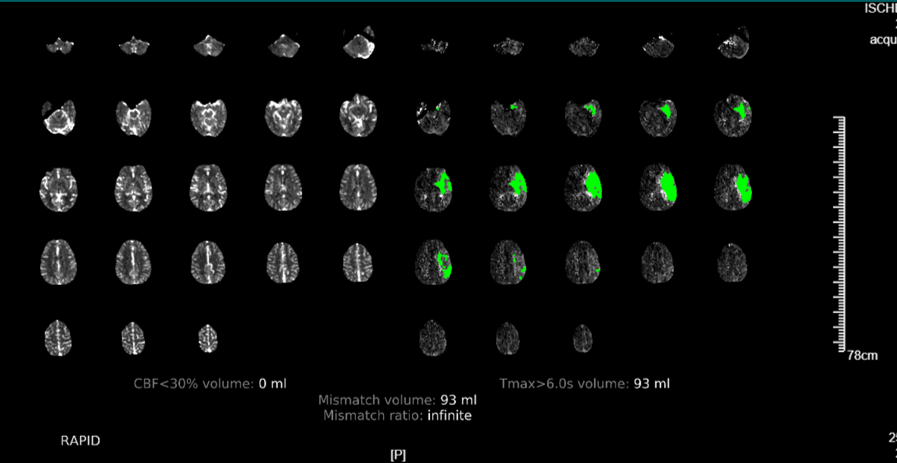

近期,我院高级卒中中心引进了脑卒中头颅“一站式”ct检查又称多模式头颅ct成像,包括ct平扫(ncct),ct血管成像(cta)和ct灌注成像(ctp)。目前省内仅有我院及中南大学湘雅医院、湘潭市中心医院三家医院应用了该项技术。该项技术的目的是扩大取栓治疗时间窗,使更多的患者从取栓治疗中获益。通俗的说,“时间就是大脑”的抢救理念倡导的是,一旦发生卒中征兆,立即送至有静脉溶栓、机械取栓资质的医院救治。对于明确发病4.5h以内的急性缺血性脑卒中患者,来了医院之后先做一个ct平扫检查,排除脑出血的情况,在无禁忌症的前提下,建议实施静脉溶栓治疗,早发现早治疗早获益。但是对于发病6-24h的患者或发病时间不明确的患者,ct平扫上是很难看到梗死表现,梗死的表现一般到24小时之后才会出现。那怎么来显示这部分组织?那就是进行“ct灌注成像”,可以看到具体的梗死区域、可挽救的缺血半暗带、同时利用ctp数据进行头部cta重建和侧枝循环评估,为下一步的治疗方案提供量化标准。但是做ct、cta再做ctp无疑时间线就拉长了,与“时间就是大脑”的理念相违背。那有没有一项技术将这三项检查紧密联系起来,有效缩短检查时间?这便是头颅“一站式”ct检查,既为脑卒中患者的救治赢得了宝贵的时间,又如同徕卡相机一样精准、高清的成像,帮助医生快速拟定治疗方案。

多模式头颅ct成像和侧枝循环评估